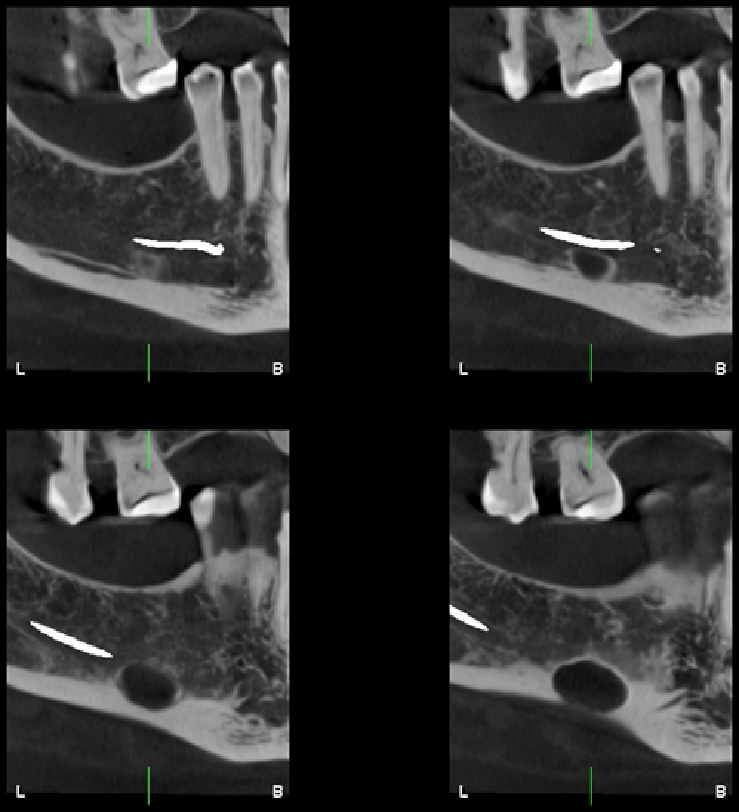

A la evaluación de la tomografía computarizada de campo mediano se observa en cortes axiales la misma imagen efectivamente parcialmente corticalizada, y que ocasiona la perdida de continuidad sólo de la tabal ósea lingual, a pesar de que en los cortes tangenciales de vestibular a lingual se asemejaría a la forma de una lesión quística en formación que se encuentra en contacto con el reborde basal, también notamos que respeta la cortical del conducto dentario inferior, finalmente en los cortes transaxiales y en la reconstrucción 3D podemos tener una mejor visión de la cavidad que no posee características patologícas y las estructuras óseas y dentarias adyacentes que no presentan alteración aparente.

CORTES TANGENCIALES